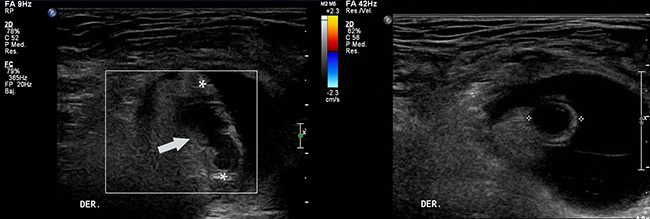

La hernia de Garengeot es una entidad rara, descrita por primera vez en 1731 por el cirujano francés Rene Jacques Croissant de Garengeot,1 quien reporta durante una exploración quirúrgica la presencia del apéndice cecal contenido dentro de una hernia femoral. Esas hernias ingresan al canal femoral ubicándose en el triángulo de Scarpa, destacándose por un mayor riesgo de complicación debido al pequeño tamaño de su anillo. Generalmente contienen intestino delgado y/o tejido adiposo visceral, siendo infrecuente la presencia del apéndice cecal (0,5-1% de los casos) y más infrecuente aún la concomitancia con apendicitis aguda (0,08-0,13% de los casos).2,3 Se presenta el caso de una mujer de 75 años con antecedentes de hipertensión arterial, dislipidemia, sarcoidosis, y derivación biliodigestiva reciente por estenosis de la vía biliar, en control y tratamiento. Consultó en el servicio de urgencia por cuadro de un día de aumento de volumen en región inguino-crural derecha asociado a dolor EVA 2/10, sin otro síntoma a la anamnesis dirigida. Cuando se realizó el examen físico, la paciente estaba afebril, destacando una masa sensible no reductible dela región crural derecha, sin otros hallazgos positivos que consignar. Los exámenes de laboratorio demostraron hematocrito 39,1%, Hb, 12,9 g/dL, leucocitos 9.600 u/mm3, neutrófilos 80%, plaquetas 242.000 u/mm3, VHS 14 mm/h. Por la sospecha clínica de una hernia crural atascada se realizó una ecografía abdominal e inguino-crural, en la cual se observó un saco herniario en relación a los vasos femorales derechos (Fig. 1), no reductible al paso del transductor, que presentaba contenido líquido y adiposo, ése último con aumento de su ecogenicidad debido a cambios inflamatorios. En su interior destacaba además la presencia de una estructura tubular de aproximadamente 10 mm de diámetro, no compresible, que no presentaba vascularización al modo Doppler color, y que se interpretó como el apéndice cecal con cambios inflamatorios (Fig. 2). Con ese diagnóstico, la paciente ingresó al pabellón quirúrgico sin realizarse otro estudio imagenológico. Durante la cirugía se identificó el saco herniario no reductible, que en su interior presentaba una estructura tubular correspondiente al apéndice cecal, el cual medía aproximadamente 11mm de diámetro, y que mostraba cambios de aspecto flegmonoso en su extremo distal. Se realizó un abordaje pre-peritoneal con ampliación del ligamento lacunar (Ligamento de Gimbernat), posteriormente reducción, apertura y resección del saco herniario. A continuación, se efectuó una apendicetomía con meso (Fig. 3) y cierre del peritoneo, para finalizar con hernioplastía primaria con dos puntos al anillo crural. La biopsia confirmó que la estructura extraída correspondía al apéndice vermiforme con hiperplasia de la mucosa, periapendicitis con hemorragia reciente y signos de organización. La paciente evolucionó en buenas condiciones, sin complicaciones postoperatorias.

Ecografía en corte longitudinal del saco herniario (A), el cual contiene una estructura tubular no vascularizada al modo Doppler color (flecha), correspondiente al apéndice cecal, asociado a un aumento de la ecogenicidad del tejido adiposo circundante (asteriscos), compatible con cambios inflamatorios. Corte transversal de la misma estructura tubular (B), la cual alcanza un diámetro máximo de 10 mm.

Pieza quirúrgica. Extracción del apéndice cecal durante procedimiento quirúrgico, el cual se encontraba aumentado de tamaño, con aspecto flegmonoso hacia la punta.